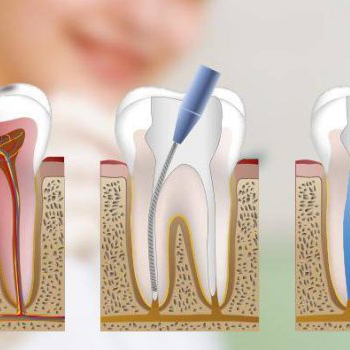

La endodoncia es la rama de la odontología especializada en tratar la patología pulpar y periapical del diente, popularmente conocida con el nombre de «matar el nervio».

Su tratamiento consiste en extraer parcial o totalmente la pulpa dental que ha sido dañada o infectada para después rellenar ese espacio con diferentes materiales. El objetivo es devolver la funcionalidad al diente y acabar con el dolor provocado por la pulpitis.